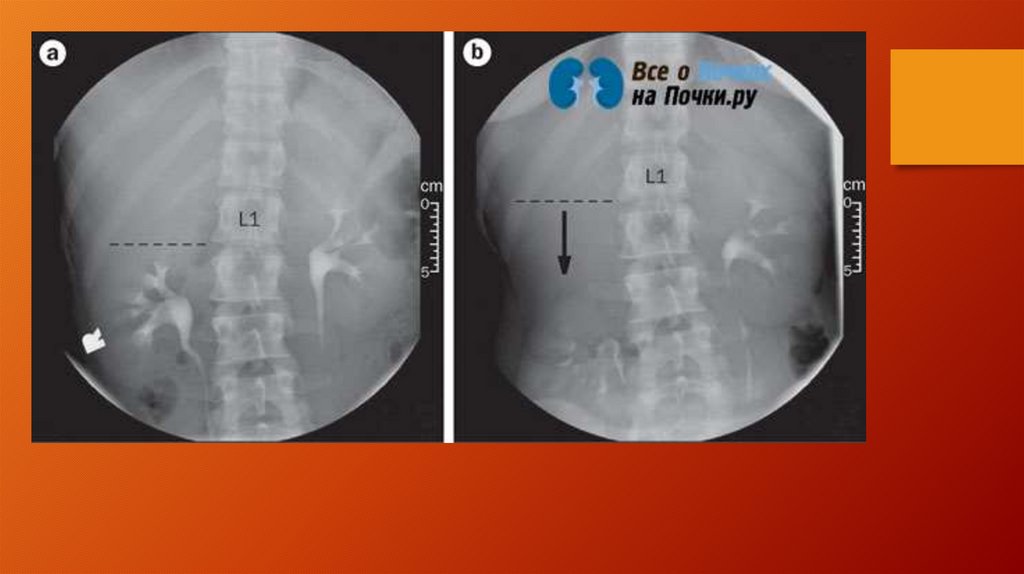

Нефроптоз

Нефроптозы (опущение почки).

У детей в 14% случаев.

Удерживающий механизм почки – связки, ложе, сосудистая

ножка.

Основное значение имеет контрастное исследование.

В 95% случаев почечная артерия на уровне поперечного

отростка L2

Почка опускается и поворачивается вокруг вертикальной и

фронтальной оси =>просвет почечной артерии уменьшается

на 50%=>вазоренальная АГ.

НА вдохе почка опускается, на выдохе принимает

окончательное положение

При нефроптозе нижний край почки ниже L3, возникает

симптом «увядающего цветка»

1 степень – без значимых изменений

2 степень – пиелоэктазия (расширение лоханки).

3 степень – гидронефроз